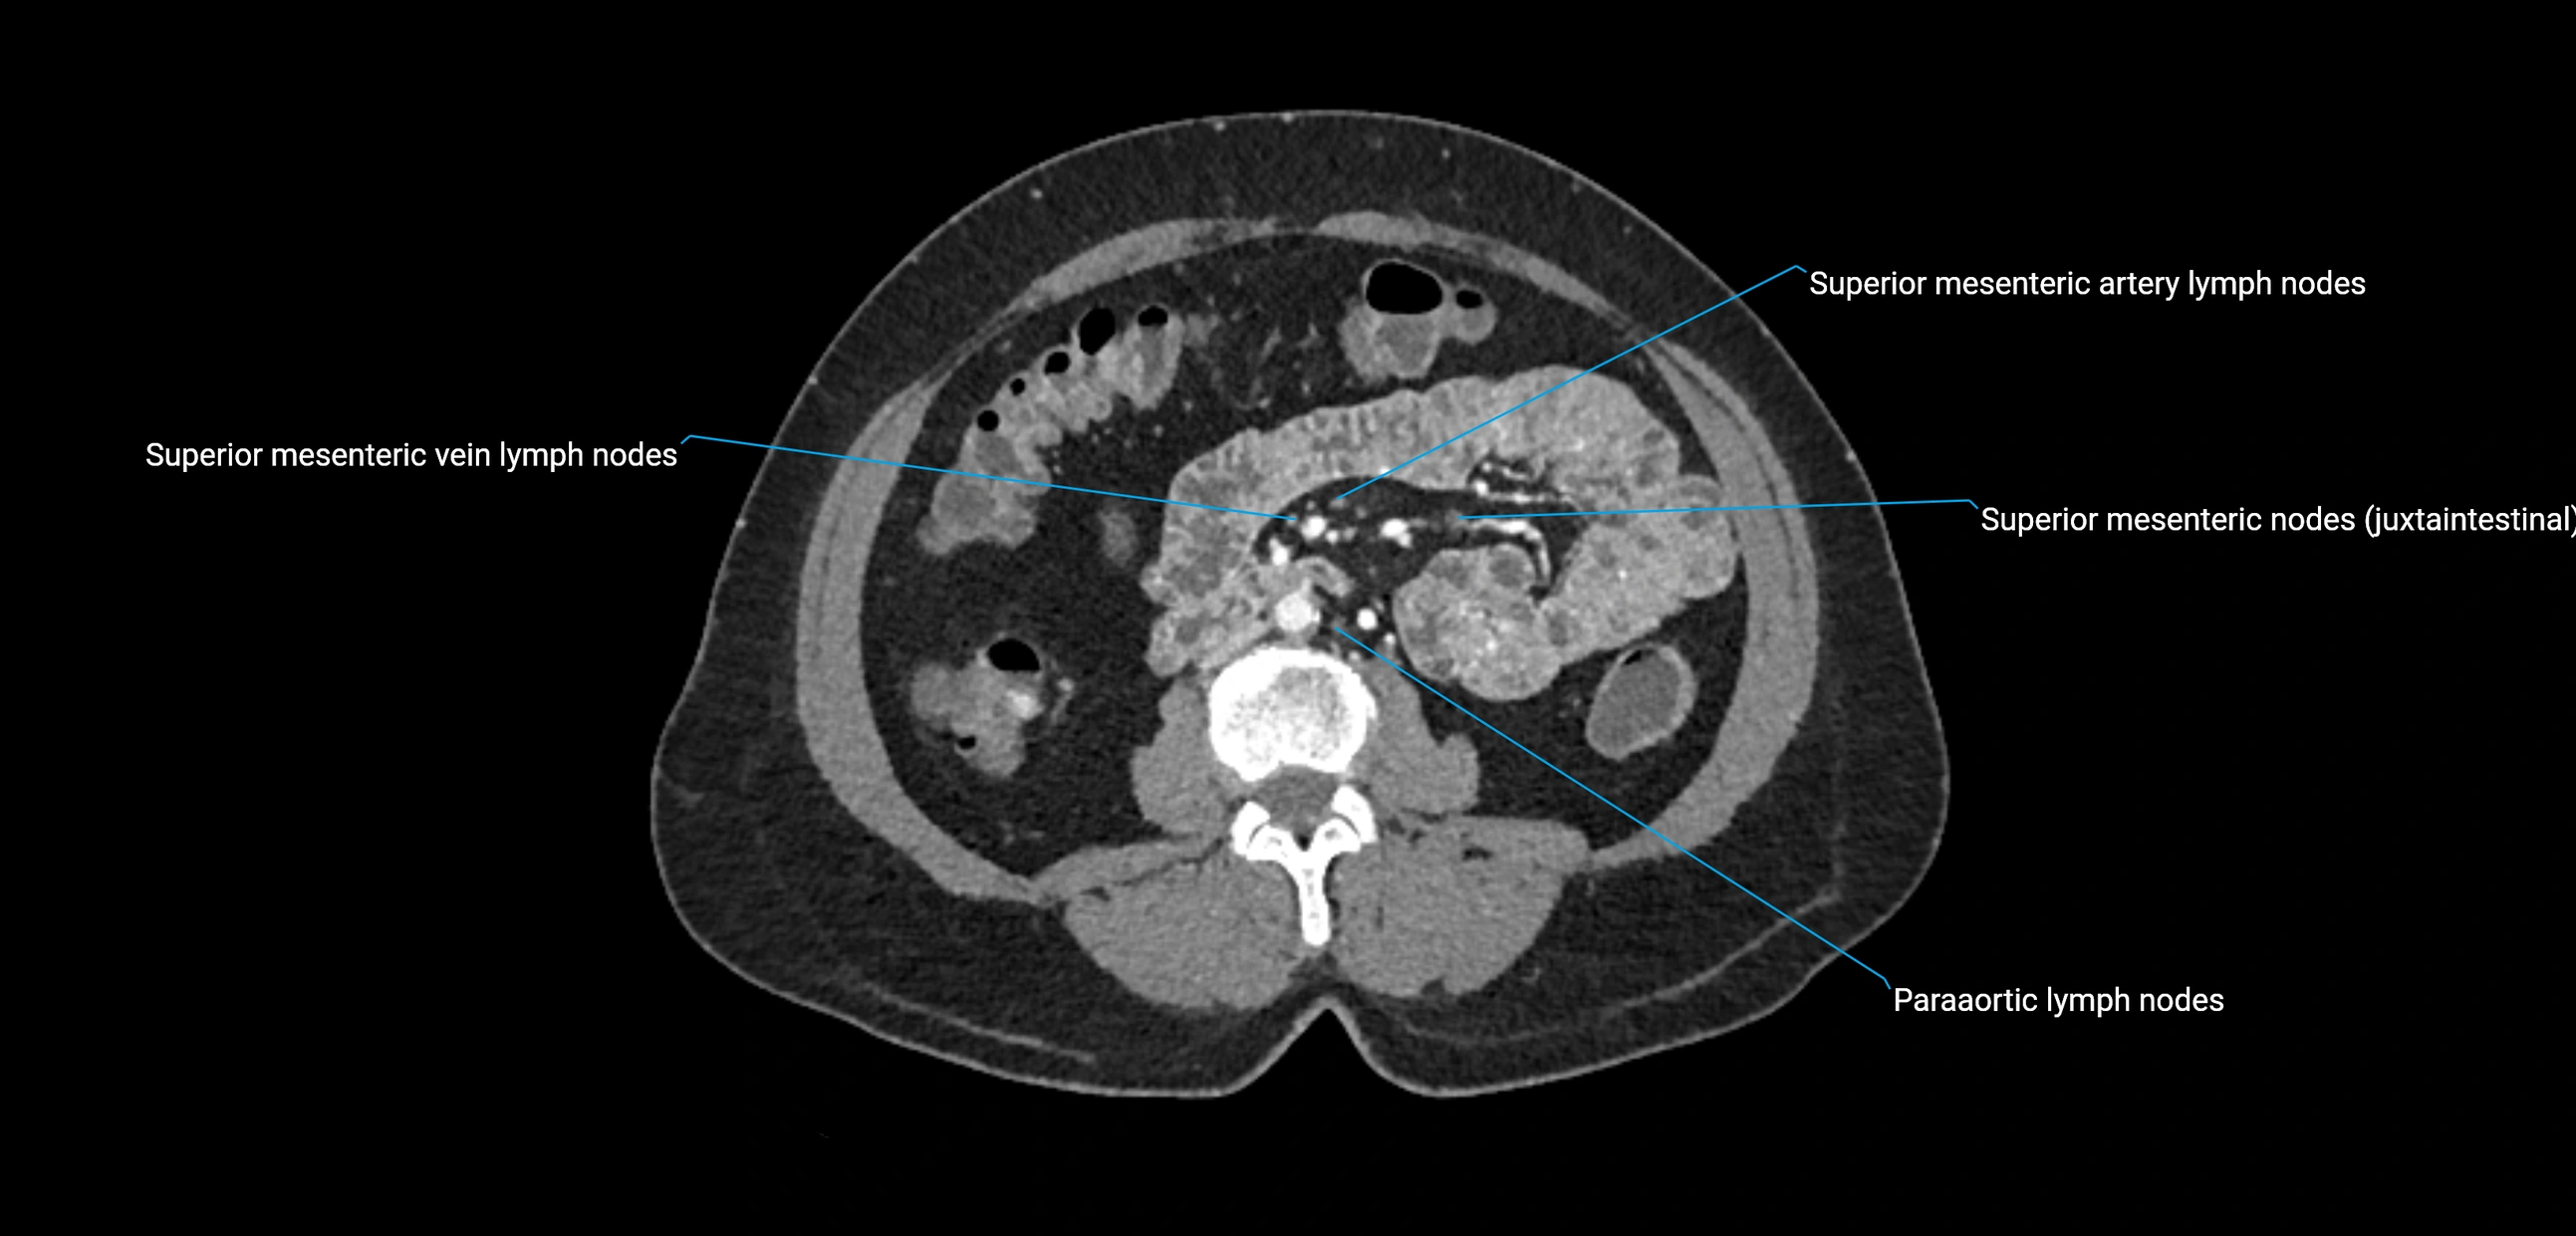

CT Appearance

CT Pre-Contrast:

• Nodes appear as soft-tissue density nodules adjacent to the aorta and IVC

• Calcification may be seen in chronic infections (e.g., tuberculosis)

CT Post-Contrast:

• Normal nodes enhance homogeneously

• Malignant nodes may show heterogeneous enhancement, central necrosis, or conglomerate formation

• Size >1 cm short axis is suspicious, though morphology and distribution are equally important

CT Venography (CTV):

• Demonstrates nodal encasement or compression of adjacent vessels (aorta, IVC, renal veins)

• Useful in staging testicular and ovarian malignancies

• Provides 3D reconstructions for retroperitoneal lymph node dissection planning